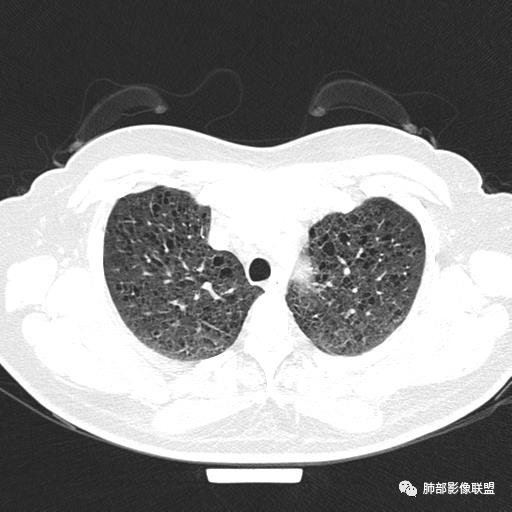

双肺弥漫囊腔,累及肋膈角,囊腔形态相对规则单一。

CT平扫示双肺弥漫分布大小不等囊状薄壁透光区,无内、中、外带分布差异,间质稍示增厚。拟LAM

女,46,活动性气喘1年。苯吸入史半年。胸部CT:两肺弥漫囊腔,上至肺尖,下至肋膈角,形态类似小囊腔。考虑:LAM,鉴别LIP,BHD,PLCH等。

双肺弥漫大小不一薄壁含气囊腔,囊间肺组织正常,正常肺背景,肺尖肺底受累;青年女性,气喘,支持LAM

CT表现:双肺弥漫大小不等的薄壁囊腔,囊壁<2mm,外形规则,血管影多位于囊腔周围,囊腔之间肺组织正常,随着疾病进展到晚期,囊腔变大、增多,不可胜数,囊腔可融合成较大的囊,与肺气肿相似,形成间质性肺纤维化。部分病例可出现结节影。